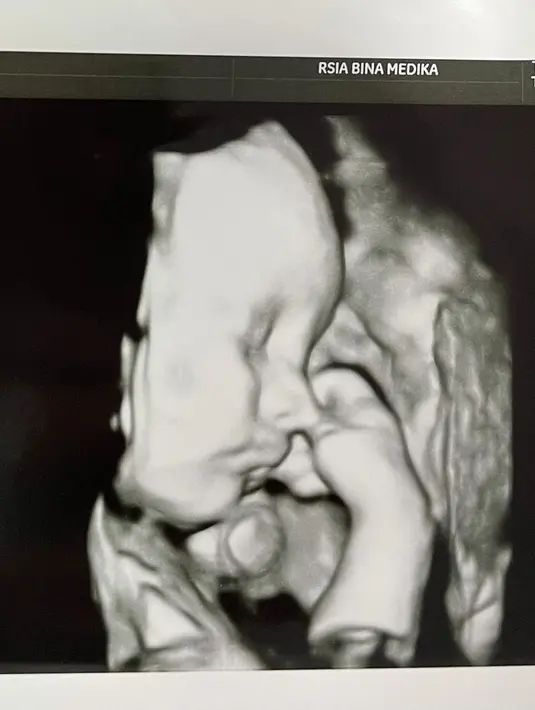

Audy Marissa dan Anthony Xie baru saja membagikan kabar bahagia dalam akun Instagram pribadinya. Rabu, 7 April 2021, Audy baru saja melahirkan anak pertama mereka di usia kandungan yang masih delapan bulan. (Instagram/audymarissa)

Di waktu dini hari, Audy menjalankan proses melahirkan secara cesar. Ia beruntung segala kondisi dalam keadaan baik, meskipun sang anak dalam kondisi prematur. Bayi laki-laki itu mereka beri nama Anzel Maverick Xie. (Instagram/audymarissa)

"7 April 2021 pukul 00.21 WIB twlah lahir anak pertama kami seorang putra yang sangat kuat, Anzel Maverick Xie secara prematur di usia kandungan 31 minggu 4 hari," tulis Audy Marissa dalam caption unggahannya. (Instagram/audymarissa)

Hingga berita ini dituliskan, bayi mungil itu masih dalam perawatan di ruang NICU. Namun Audy bersyukur lantaran kondisi anaknya dalam keadaan yang baik. (Instagram/audymarissa)

"Kami sangat bersyukur baby Anzel semua organnya baik dan bagus. Tapi masih terus harus dipantau di ruang NICU. Jadi mama belum bisa peluk langsung," tambahnya. (Instagram/audymarissa)